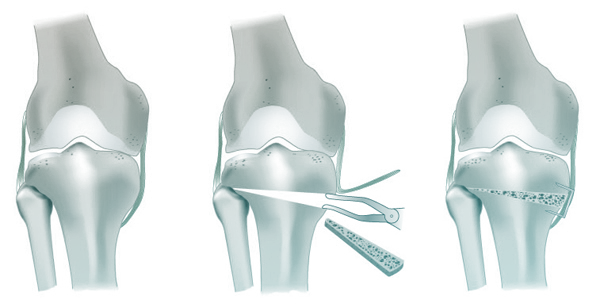

L’objectif est de corriger l’axe de votre jambe pour déplacer le poids du corps vers la partie saine du genou, soulageant ainsi la zone usée.

L’intervention dure environ une heure. Je réalise une coupure partielle du tibia (ostéotomie) pour l’ouvrir et redresser l’axe. Cette ouverture est maintenue par une plaque vissée et comblée par un substitut osseux ou une greffe.